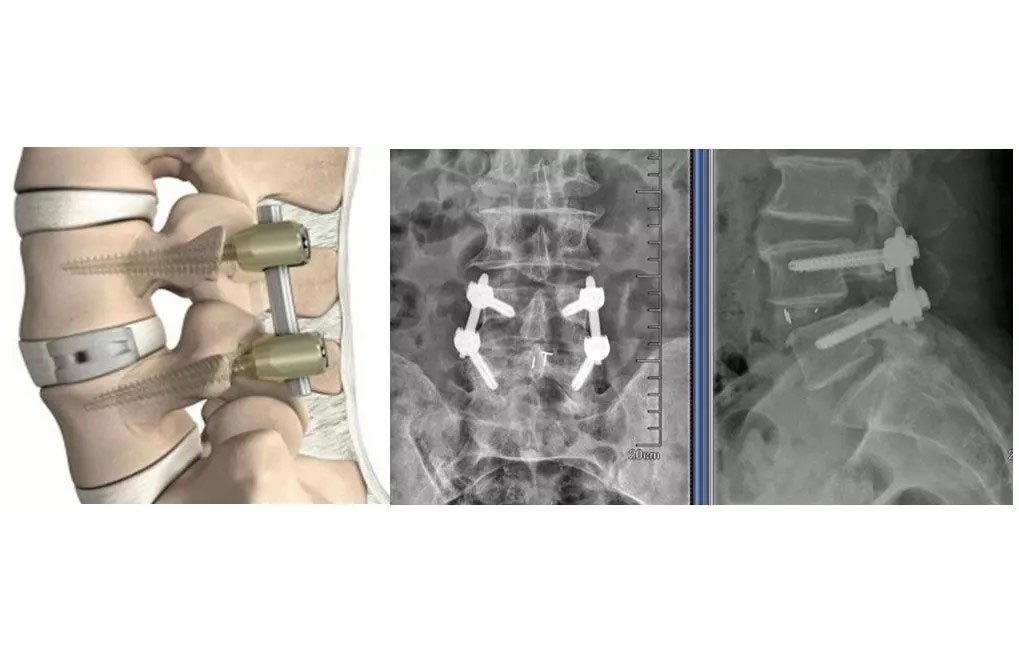

图例为腰间盘损伤置换

通过外科手术的方式,将椎弓根钉打入发生侧弯的椎体,安装内固定装置,复位固定(钢丝钳拉直连接杆),拧紧螺母固定钉棒,然后冲洗伤口止血缝合,伤口较大,内固定支架需要跟随身体很长一段时间

比较新的微创手术过程示意